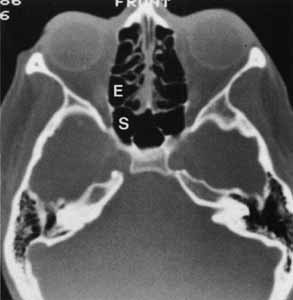

The nasal cavity is bisected anteriorly by the cartilage and septum, which joins the vomer, a bony vertical plate of ethmoid, posteriorly. Laterally, the nasal wall is thrown into three or more horizontal ridges termed turbinates, with spaces below each with corresponding names (Fig. 5). The inferior turbinate is the largest ridge, whereas the progressively smaller and more posterior middle, superior, and supreme turbinates (sometimes present) are outcroppings of the ethmoid bone. The large cartilaginous anterior dilatation of the nose is the nasal vestibule. When the exterior nares are dilated by a nasal speculum, the inferior turbinate and inferior meatus can be seen by tilting the blades to look along the nasal floor. The middle turbinate and nasal atrium are seen, if the examiner does not forcibly rotate the blades. Because the atrium wall is convex medially, an external dacryocystorhinostomy site located at the anterior or inferior tip of the middle turbinate may not be directly visualized. A dacryocystorhinostomy achieved by the endoscopic laser–assisted approach is usually more inferior and posterior to the routine external site.5 The nasolacrimal duct drains under the inferior turbinate, whereas the frontonasal duct from the frontal sinus drains into the anterior middle meatus. Within the middle meatus posterior to the atrium lies a curvilinear ridge, the uncinate process, with the hiatus semilunaris depression behind, which houses the ostium of the maxillary sinus (see Fig. 5).6 The paranasal sinuses more than double the nasal chamber volume. The vascular mucoperiosteum of the nose is carried into the sinuses, where densely populated cilia rhythmically beat mucus toward the ostium. Acute inflammation of the nasal and paranasal mucoperiosteum can result in swelling severe enough to occlude the sinus ostia, and thus purulent sinusitis may result. Chronic sinusitis may lead to permanent occlusion of the ostia, which can result in mucocele formation. The maxillary sinus is the largest of the paranasal sinuses (15 cc). This sinus roof is the orbital floor that declines from the medial wall to the lateral wall at an angle of approximately 30 degrees. Like the medial sinus roof, the lateral wall of the sinus is also thin and subject to fracture with zygomatic displacement. The maxillary sinus drains into the middle meatus through an ostium located near the level of the orbital floor, thus orbital tissues that are displaced in surgery or trauma may obstruct the ostium. The pterygoid-palatine space lies posterior to the maxillary sinus with the internal maxillary artery intimately related to the posterior sinus wall. As mentioned previously, the ethmoidals are the most exuberant growing sinuses and may pneumatize the frontal, sphenoid, palatine, and lacrimal bones. The ethmoid sinuses are shaped like a box slightly wider posteriorly where it articulates with the sphenoid (see Fig. 4). The anterior and middle ethmoidals drain into the middle meatus, whereas the posterior cells may drain into the superior meatus. The roof of the orbit slopes down as it travels medially, and this slope continues at the frontoethmoidal suture to become the ethmoid roof (fovea ethmoidalis), and finally to overlie the nasal cavity as the cribriform plate. The crista galli bisects the cribriform plate above and continues below as the vertical nasal plate (vomer). Three to fifteen air cells expand from each lateral border to the cribriform plate, and the air cell masses convolute medially to form the middle, superior, and supreme (if present) turbinates. The surgeon should be aware of the anatomic relationship of anterior ethmoid air cells to the lacrimal sac fossa when performing external dacryocystorhinostomy. Blaylock7 evaluated computed tomographic scans of 190 orbits with normal ethmoid anatomy and found that in 93% of the orbits, the cells extended anterior to the posterior lacrimal crest, with 40% entering the frontal process of the maxilla. The frontal sinus is not well developed or radiographically evident until about the 6th year of life. Frontal sinus expansion continues until early adulthood and attains greater proportions in the male. The frontal sinus lies deep to the superior orbital rim and drains into the middle meatus via the frontonasal duct. Each sinus is a single chamber with intrasinus septae, which give it a scalloped appearance radiologically. The frontal sinus is a common site for mucocele development. The sphenoid sinus also continues to grow until adulthood with varying degrees of pneumatization. It drains into the sphenoethmoid recess under the superior turbinate. In the instance where the sphenoid body is fully pneumatized, only sinus mucoperiosteum, a thin layer of bone, and periosteum separate the respiratory tract from the overlying internal carotid artery, the cavernous sinus, and branches of the trigeminal nerve. |